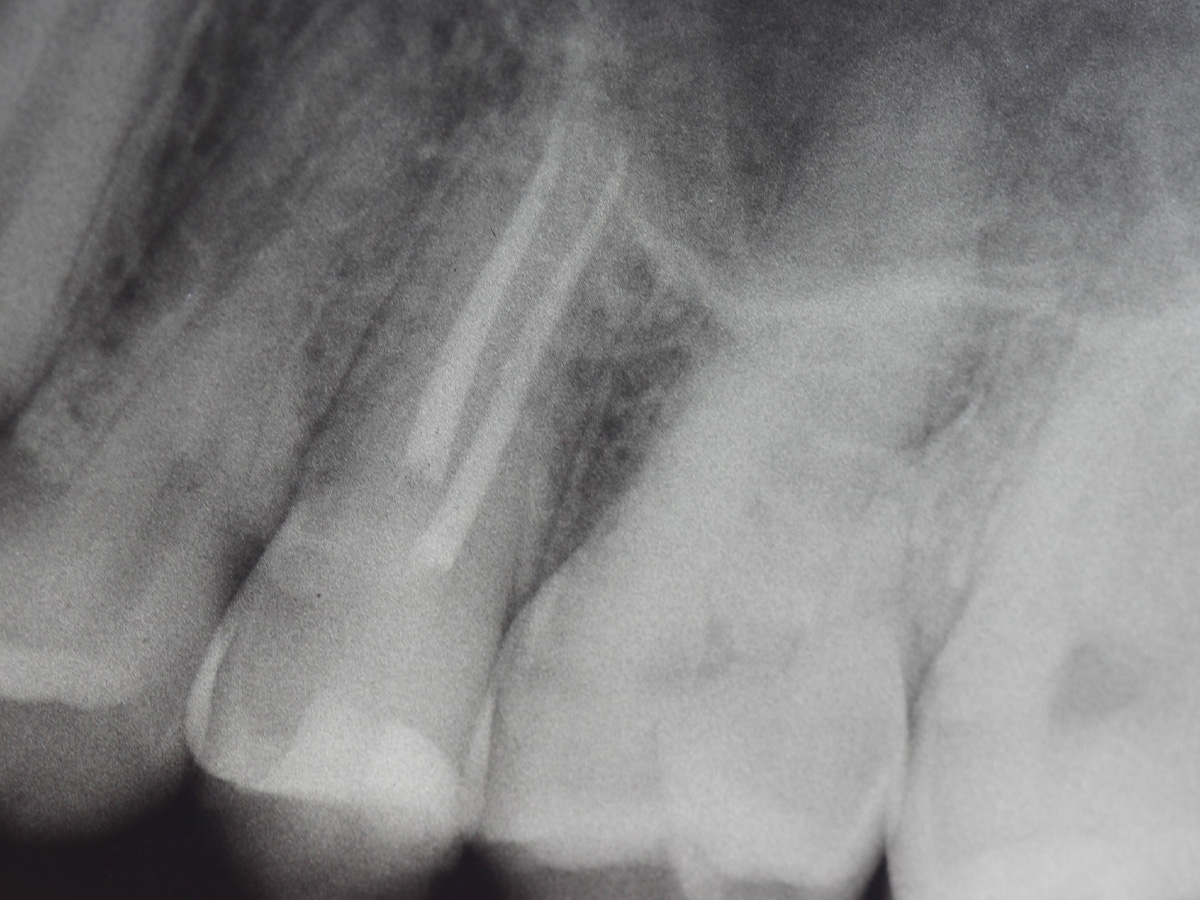

Abbildung 1

Bissflügelröntgenaufnahme, Approximalraumkaries an Zahn 25 distal